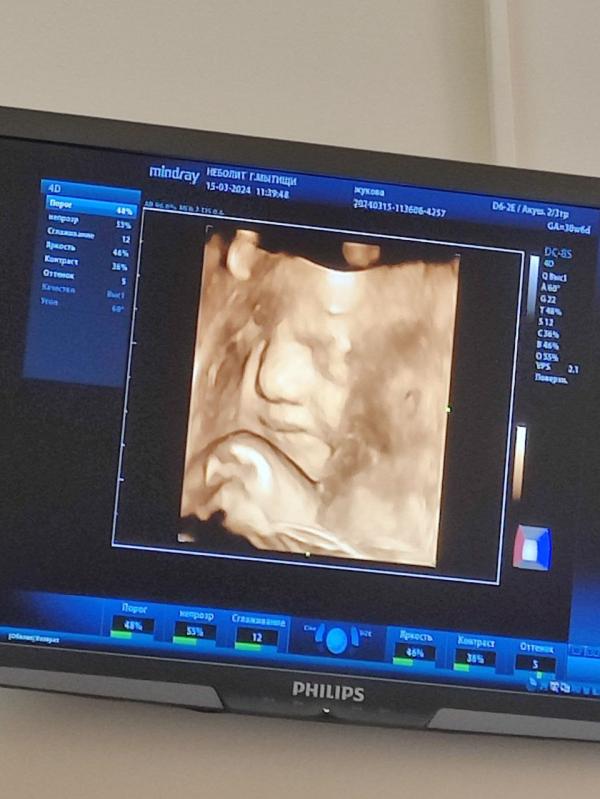

И вот наша дамочка с таким выдающимся носом, все его отметили) шуточки льются от всех рекой😂

Вроде бы маленькая дама внутри меня уже показала все умелки: презренно один глаз открыла, улыбнулась,губы надула, палец пососала, рот открыла, воды глотнула, танцы локтями продемонстрировала 😂